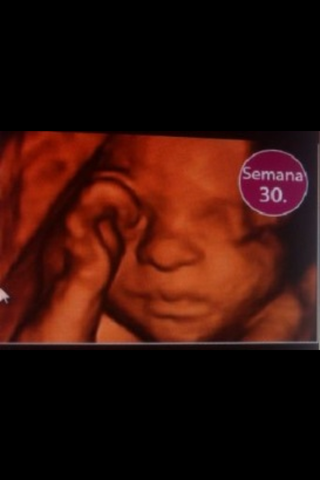

Él bebe ya tiene pestañas

Sus medidas son de 22 cm y su peso alrededor de 1k